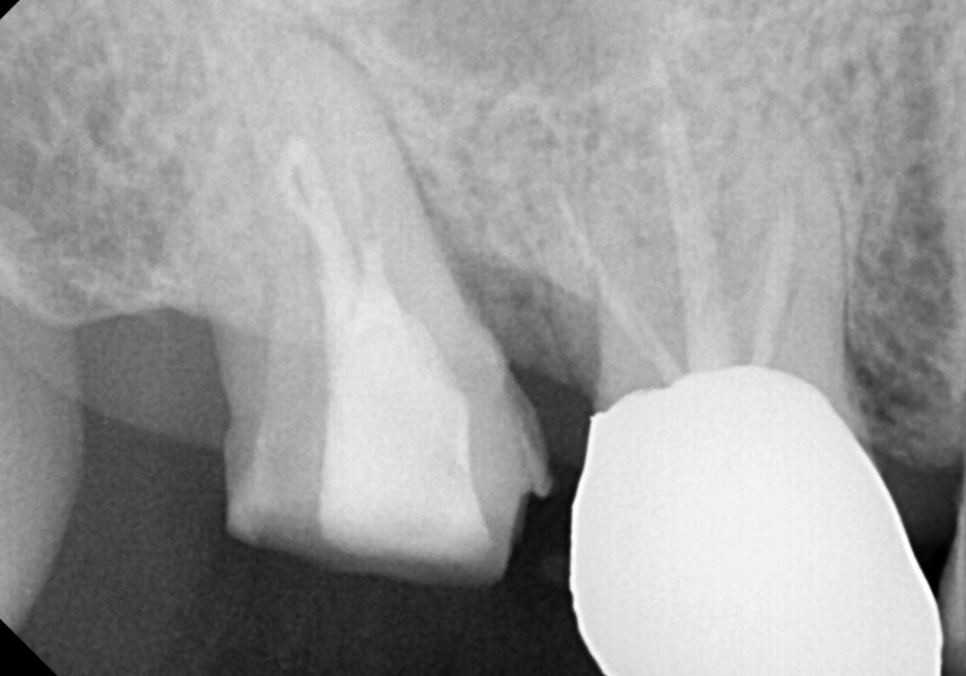

본격적인 신경치료를 위해

먼저 와동형성 과정을 거쳤습니다.

용어가 조금 생소하시죠?

쉽게 말해,

치아 내부에 숨어 있는 신경관에

안전하게 도달하기 위해

치아머리 부분에 작은 입구(구멍)를

만드는 작업을 뜻해요.

240229

이 구멍을 통해 치아 내부를 들여다보니,

겉에서 보던 것보다 실금이 더 깊고

선명하게 이어져 있네요..

자칫하면 뿌리까지 이어져

치아가 반으로 갈라질 수도 있는 상황..

환자분의 통증을 잡기 위해

오염된 신경을 깨끗하게 제거하고,

240308

세균이 침투했을지 모를 신경관 내부를

소독하는 과정을 2~3번에 걸쳐

꼼꼼히 진행했어요.